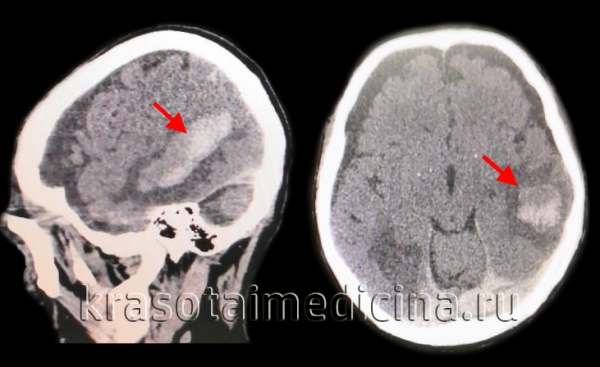

КТ головного мозга. Геморрагический инсульт, обширная интрапаренхиматозная гематома в левой гемисфере

Они позволяют определить объем и локализацию внутримозговой гематомы, степень дислокации мозга и сопутствующего отека, наличие и область распространения кровоизлияния. Желательно проведение повторных КТ-исследований, чтобы проследить эволюцию гематомы и состояние мозговой ткани в динамике.